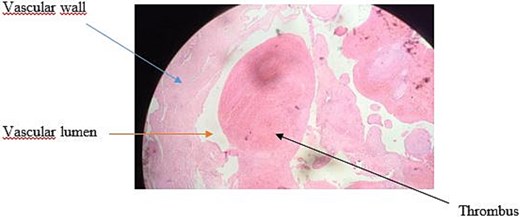

Doppler ultrasound of the mass revealed a 19 mm ovoid formation in the right hemi-mandibular region, with arterial waveforms and likely afferent and efferent arteries. Craniocervical computed tomography (CT) (Fig. 1a–c) confirmed a saccular aneurysm of the right facial artery, measuring 23.9 × 17 mm, thrombosed in two-thirds of its lumen.

CT images illustrating the right facial artery aneurysm: (a) 3D-reconstructed CT scan highlighting the aneurysm. (b) Preoperative contrast-enhanced CT with 3D reconstruction indicating the aneurysm. (c) Preoperative axial contrast-enhanced CT demonstrating the saccular aneurysm of the right facial artery and its measurements.